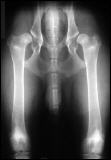

Schwere Hüftgelenksdysplasie